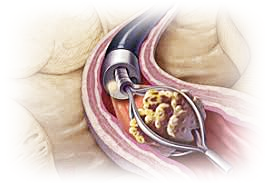

요도에 박힌 돌을 밀어냅니다.

요관은 지렁이처럼 서로 단단히 얽혀 있습니다.